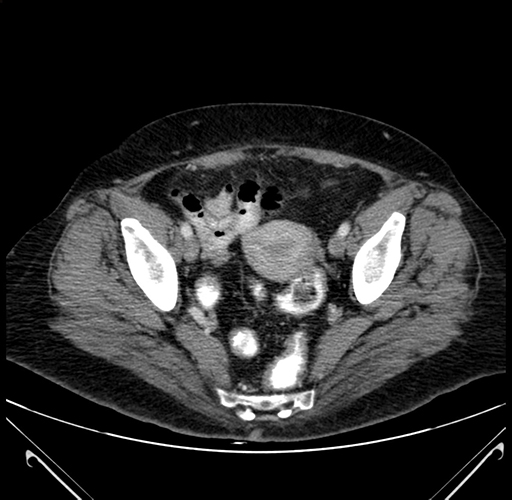

Pre-Chemo: Axial Venous

Axial Venous